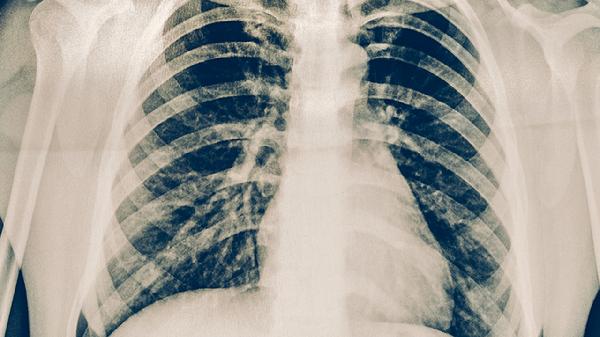

肺結核可通過抗結核藥物治療、手術治療、營養(yǎng)支持治療、心理干預、隔離防護等方式治療。肺結核是由結核分枝桿菌感染引起的慢性傳染病,主要表現(xiàn)為咳嗽、咳痰、低熱、盜汗等癥狀。1、抗結核藥物治療抗結核藥物治療是肺結核的主要治療方法,常用藥物包括異煙肼片、利福平膠囊、吡嗪酰胺片、乙胺丁醇片、鏈霉素注射液等。這些藥物需要聯(lián)合使用,遵循早期、聯(lián)合、適量、規(guī)律、全程的治療原則...

肺結核可通過藥物治療、手術治療、營養(yǎng)支持、隔離防護、心理疏導等方式治療。肺結核通常由結核分枝桿菌感染引起,主要表現(xiàn)為咳嗽、咳痰、發(fā)熱、盜汗等癥狀。1、藥物治療肺結核的藥物治療以抗結核藥物為主,常用藥物包括異煙肼片、利福平膠囊、吡嗪酰胺片、乙胺丁醇片、鏈霉素注射液等。這些藥物需要聯(lián)合使用,遵循早期、規(guī)律、全程、適量、聯(lián)合的原則。藥物治療通常分為強化期和鞏固期,...

肺結核可通過抗結核藥物治療、手術治療、營養(yǎng)支持、隔離防護、定期復查等方式治療。肺結核通常由結核分枝桿菌感染引起,主要表現(xiàn)為咳嗽、咳痰、低熱、盜汗、乏力等癥狀。1、抗結核藥物治療抗結核藥物治療是肺結核的主要治療方式,常用藥物包括異煙肼片、利福平膠囊、吡嗪酰胺片、乙胺丁醇片、鏈霉素注射液等。這些藥物需要聯(lián)合使用,遵循早期、規(guī)律、全程、適量、聯(lián)合的原則。異煙肼片能...